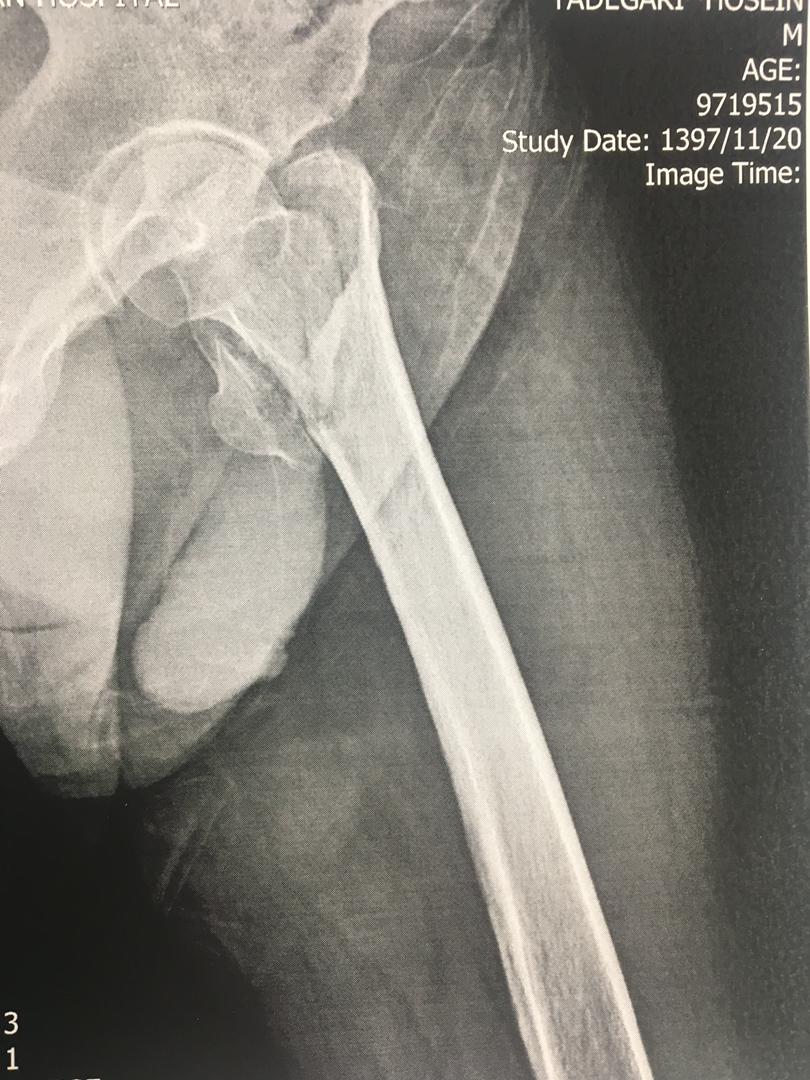

اقای 50 ساله با شکستگی خرد شده ی ران که جراحی و بهبودی کامل